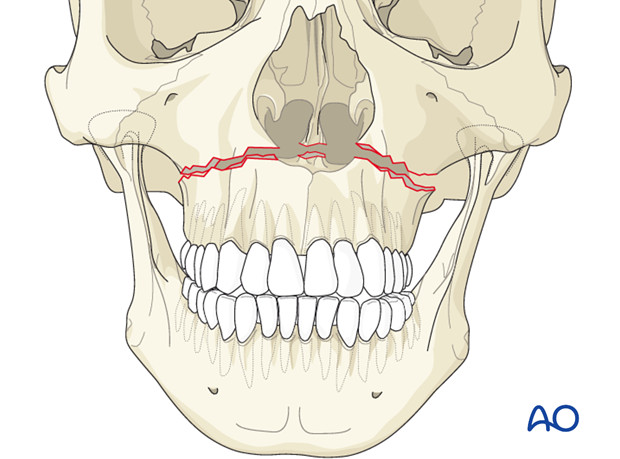

Fraktur Maksila

Fraktur maksila adalah salah satu fraktur pada daerah wajah.